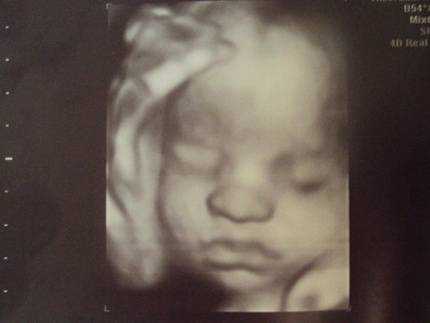

На 29 неделе беременности на головке у малыша уже видны волосики. Сейчас они напоминают скорее пушок. Вместе с этим, пушок, который присутствовал на теле (лануго), исчезает. Уменьшается также количество защитной смазки. С каждым днем увеличивается жировая прокладка и малыш все больше становится похожим на новорожденного. Кожа приобретает светло-розовый оттенок, появляются так называемые младенческие складочки и милая припухлость на щечках.

Внешне, ребенок на 29 неделе беременности выглядит почти так же, как после рождения. Пушок на его коже начинает исчезать, а количество первородной смазки уменьшается к моменту родов. Доля подкожного жира на этой неделе ничтожно мала – около 4%. Однако, по мере роста плода, жировая клетчатка будет активно нарастать, что способствует гладкости кожи.

В период когда развитие беременности составляет 29 недель, то малыш на этом сроке активно накапливает белый жир и набирает в весе. У малютки сейчас можно наблюдать появление пухленьких щечек, здесь в первую очередь будет откладываться жир, но и теряться, что интересно, также здесь. Так задумано было природой для того, чтобы максимально поддержать самую важную способность в первый год жизни крохи — сосание материнской груди.

На 29 неделе беременности малыш выглядит уже почти как новорожденный. Набирать вес и готовить к самостоятельной большой работе легкие — вот основная задача ребенка на последние недели беременности. У малыша на этом сроке уже сформированы зрение, слух, вкус и обоняние, он может различать свет и тьму, но полностью сфокусировать зрение ему еще пока не удается. Умение это в полной мере покорится малышу к моменту появления на свет.

Сейчас плод уже может чувствовать и вкус и запах околоплодных вод; различать свет и звуки; он полностью чувствует настроение и общее состояние матери; может сфокусировать свой взгляд на чем-то одном. Внешне малыш уже начинает походить на новорожденного кроху: его кожный покров светлеет и выравнивается, лануго постепенно начинает сходить, а количество смазки минимизируется. Подкожного жира становится больше и чем ближе к дате родов, тем больше милых складочек образуется на теле ребеночка.

Щечки постепенно округляются вместе с другими частями тела. Так как половые органы сформировались достаточно хорошо, на УЗИ можно уже безошибочно определить пол малыша. С каждым днем организм ребенка начинает функционировать все лучше, превращаясь в гармоничную отлаженную систему. Связки и мышцы продолжают совершенствоваться и крепчать, что ощущается по силе толчков. Учитывая то, что места для кувырканий становится намного меньше, каждый переворот с головы на ноги и наоборот будет четко ощущаться мамочкой.